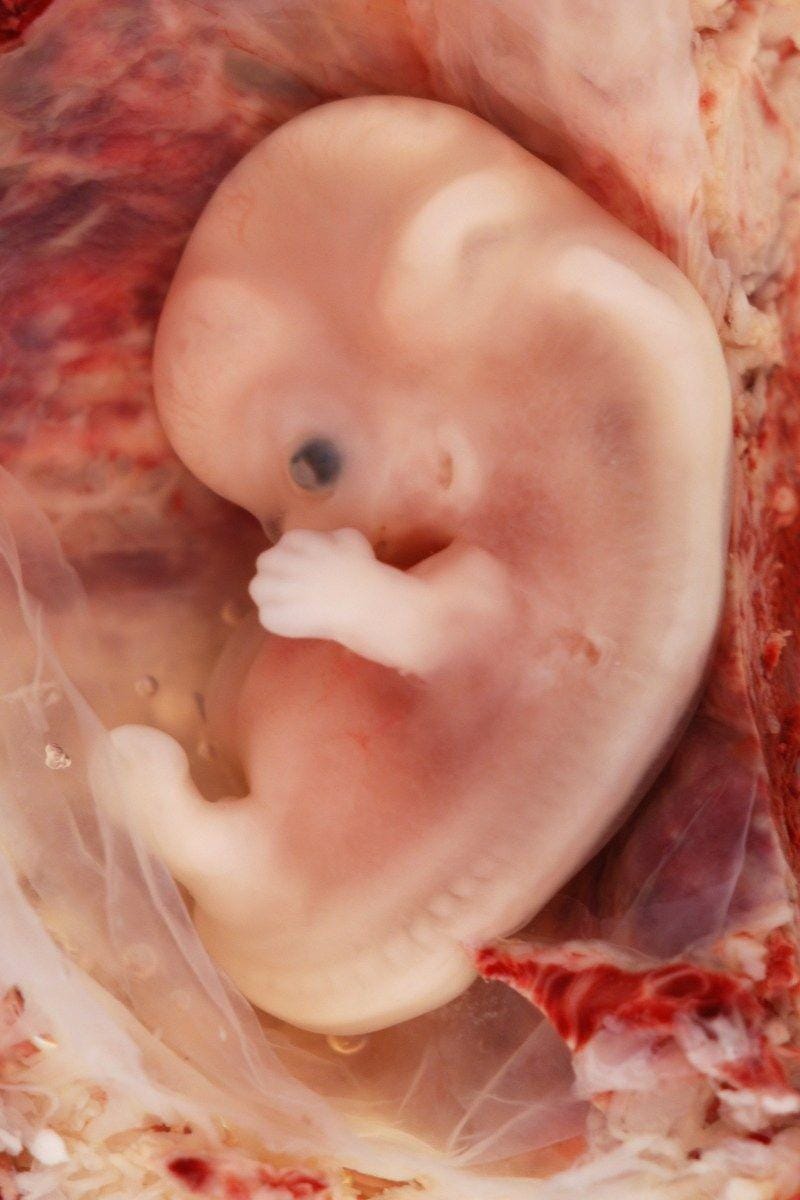

3. Tulang belakang, plasenta, dan otak

Pada sekitar minggu ketiga hingga keenam, bentuk tubuh fetus akan mulai terbentuk. Pada awalnya, akan terbentuk beberapa lapisan sel yang bervariasi. Kemudian sebuah titik kecil yang tersambung pada garis seperti benang akan tumbuh. Itulah awal dari otak dan tulang belakang. Pada saat yang sama, plasenta, tempat tumbuhnya bayi juga terbentuk.

4. Jantung

Yang menggerakkan sel untuk berkembang adalah DNA kita. Setelah enam minggu kehamilan, DNA akan memerintahkan jaringan untuk membentuk jantung. Pada saat itu, jantung kita akan terlihat seperti pusat tubuh yang berbentuk tabung kecil. Jaringan mulai bergerak dan memompa, membuat detak jantung.

5. Tangan dan kaki

Urutan berikutnya adalah tumbuhnya kaki dan tangan. Eits, jangan membayangkan tangan dan kaki kita yang seperti saat ini ya. Bentuknya masih abstrak, hanya seperti bulatan kecil. Pertumbuhan ini dimulai pada kehamilan usia lima hingga delapan bulan. Setelah lebih dari 10 minggu, barulah muncul tangan dan kaki yang sesungguhnya.

6. Wajah dan mata

Di tahap ini, sel tubuh secara perlahan membentuk fitur-fitur wajar yang masih kasar. Permukaan kepala akan membuka menjadi mulut, bagian hidung dan dahi juga mulai terbentuk. Setelahnya, dua titik gelap kecil mulai terlihat di bagian samping-samping kepala. Itu adalah awal dari pembentukan mata. Seiring pertumbuhan, kedua titik mendekat dan berada di bagian depan kepala.